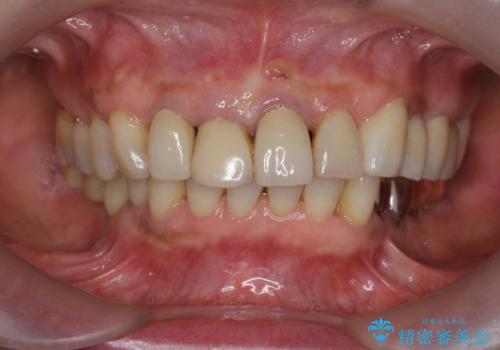

2. ぐらつく前歯 ブリッジ治療の治療中